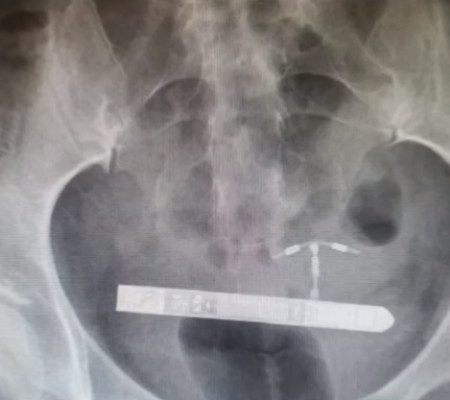

Assim que chegou ao hospital, ela foi encaminhada para uma sala de emergência e fez diversos exames pélvicos para que os médicos se certificassem da localização exata do vibrador.

"Nós da equipe médica não conseguimos encontra-lo na vagina", relembrou o ginecologista Greg Marchand, que logo depois a submeteu a um exame de raio x. "Fiquei surpreso quando percebi que ele estava na bexiga da paciente".

Os médicos determinaram então que o brinquedo sexual tinha penetrado no seu corpo através da uretra e se alojado ao lado da bexiga. Foi feita uma cirurgia para removê-lo e, após a recuperação, a mulher pretende entrar com uma ação contra a empresa.